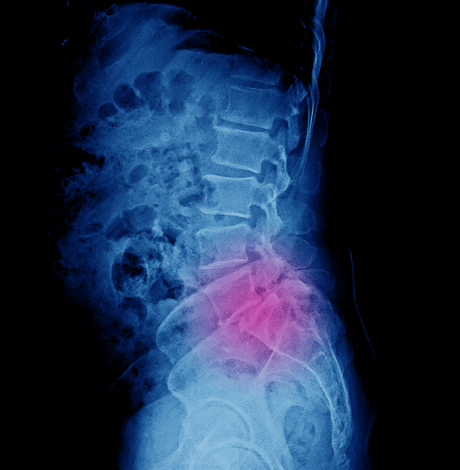

It is a surgical technique to join two or more vertebrae to ease the pressure on the spine. It can be performed in any section of the spine that causes discomfort to the patient.

- X-ray: To check for arthritis, injuries to the vertebrae.